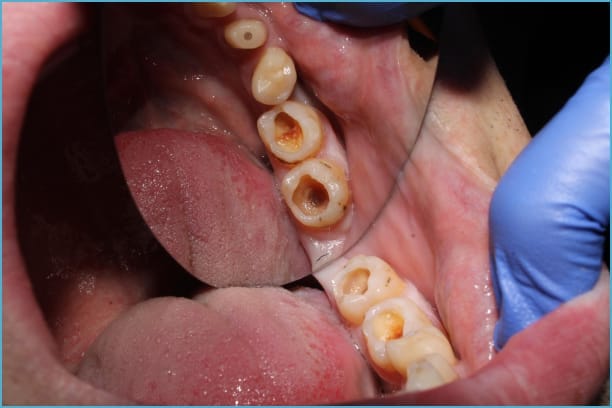

Once decay breaches your tooth enamel, it reaches the dentin – a softer, more sensitive layer of your tooth. At this stage, discomfort becomes more noticeable. You’ll likely experience sharp pain when consuming hot, cold, or sweet items. The decay progresses faster now because dentin is softer than enamel.

Your tooth may develop visible cavities or dark spots. The structural integrity of your tooth weakens, making it more susceptible to cracking or breaking during normal chewing.